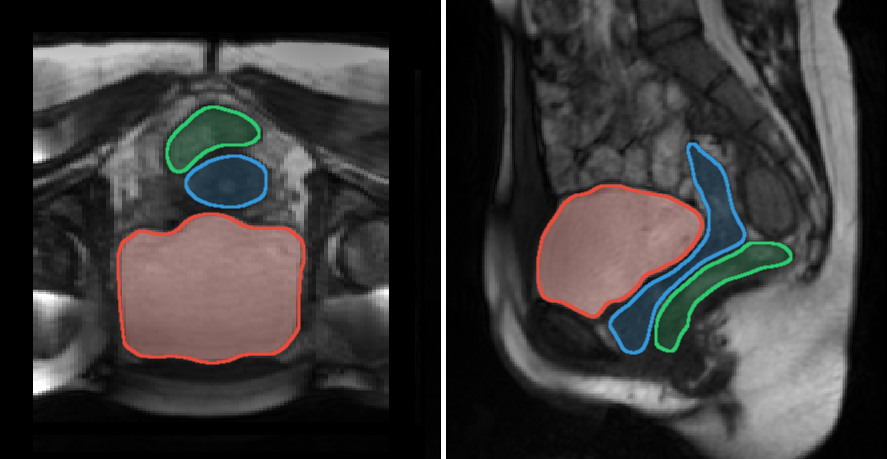

Reconstructed volumes over skeletons and projections of the associated Jacobian maps are available for two subjects as supporting materials. Projections of the maps on meshes of the static reference volumes are shown in Fig. 7 for each subject and each configuration. Visualizations were performed using the Anatomist software [36]. At each point, the value for the intersection between the mesh of the static reference volume and the map, was estimated as the mean of the values within a sphere of 4 mm radius, almost 3 voxels, around the intersection point. This projection scheme was common to all configurations to provide a common reference for comparison regardless the resolutions of the reconstructed volumes. The reddest areas indicate the locations that underwent the largest deformations during the loading exercises. Note that volume scales are not the same for each subject in Fig. 7, e.g. bladder volume was 48 cm3 for subject 7 whereas it was 403 cm3 for subject 8.

Forced breathing exercises with maximum contraction are hardly reproducible for untrained subjects. Deformation magnitudes were different for each dynamic sequence and consequently differed for each geometric configuration . For instance, in Fig. 7, subjects 4 and 5 did not exert the same intensities during each loading exercise explaining the main scale differences. On the whole, no visual correlation can be done between geometry configuration and amplitude of the deformations. Dynamic sequences with the highest deformation characteristics are for subjects 1, 2, 7, and 8, for subjects 3, 4, and 5, and for subject 6. Intra-subject comparison of deformation amplitudes might not be relevant and was not the focus of our study. However, regardless of the load magnitude applied to the bladder, the intra-subject locations of the most deformed tissue areas are quite similar between dynamic sequences. Overall, tissue areas that have undergone deformities are located on the anterior and superior parts of bladders due to the abdominal viscera pushing against the bladder during loading exercises. Few deformation zones are visible on the inferior part due to a strong pelvic floor in our young healthy volunteers. However, inferior deformations in patients could indicate pelvic floor weaknesses.